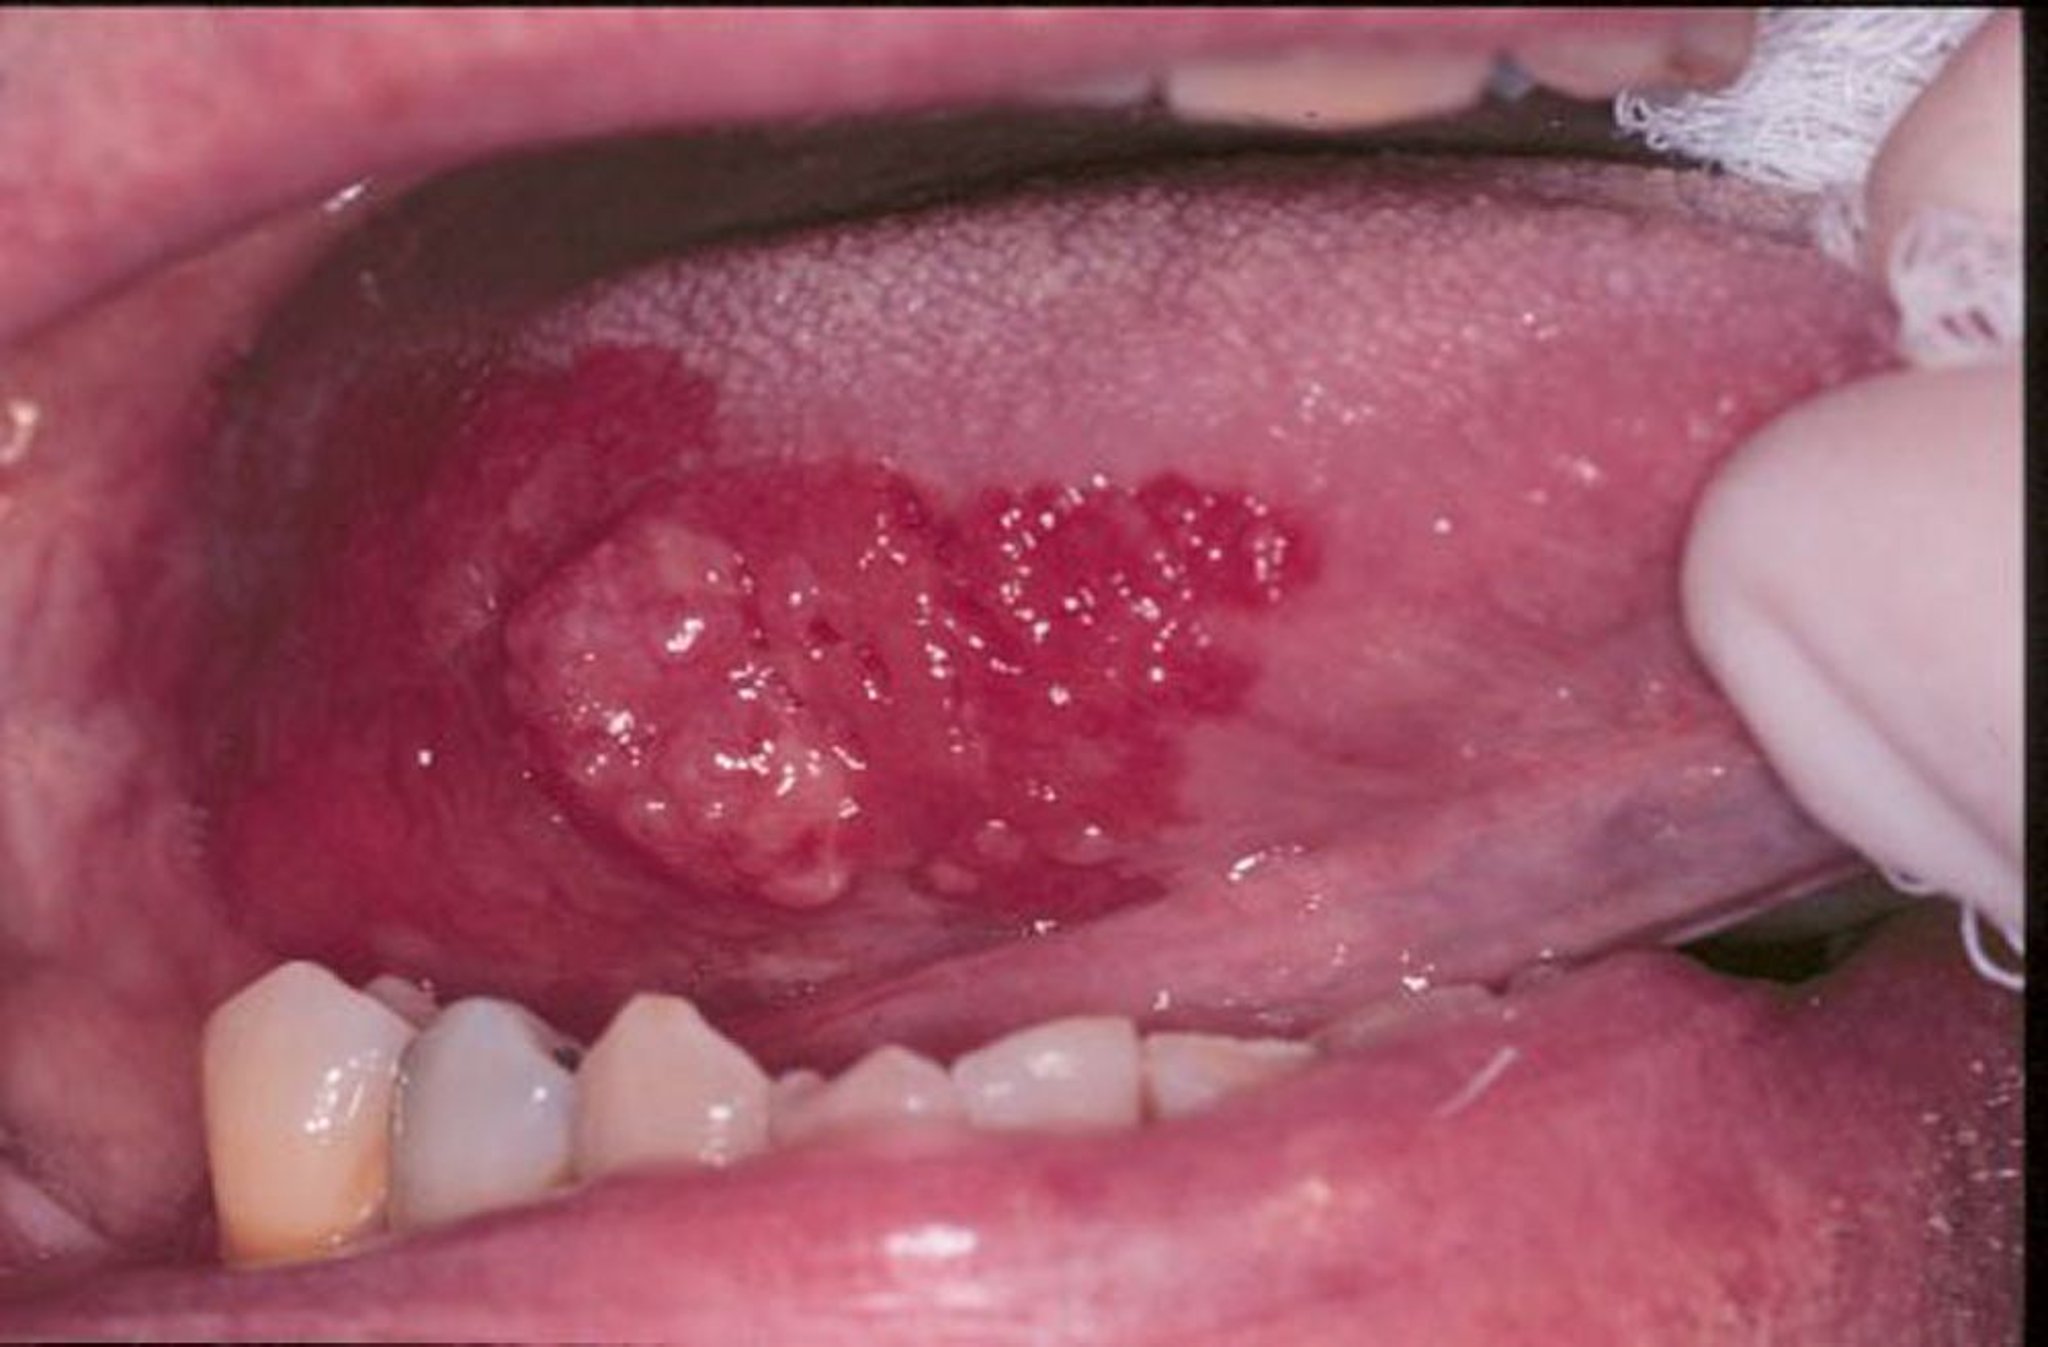

Hồng sản và ung thư biểu mô tế bào vảy

Hồng sản là một thuật ngữ chung có thể dùng để mô tả các tổn thương màu đỏ, phẳng hoặc bị trợt phát triển trong miệng. Trong hình ảnh này, ung thư biểu mô tế bào vảy được bao quanh bởi một rìa hồng sản.

Hình ảnh do bác sĩ nha khoa Jonathan A. Ship cung cấp.